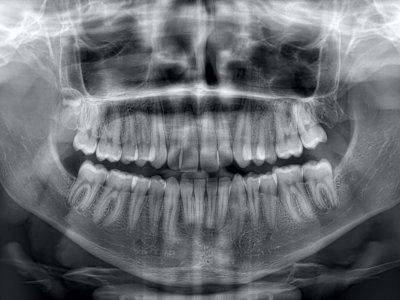

PANORAMİK RÖNTGEN

Tedavi planlamasının daha hızlı, doğru ve kapsamlı bir şekilde oluşturulmasına olanak tanıyan röntgen görüntüleridir.